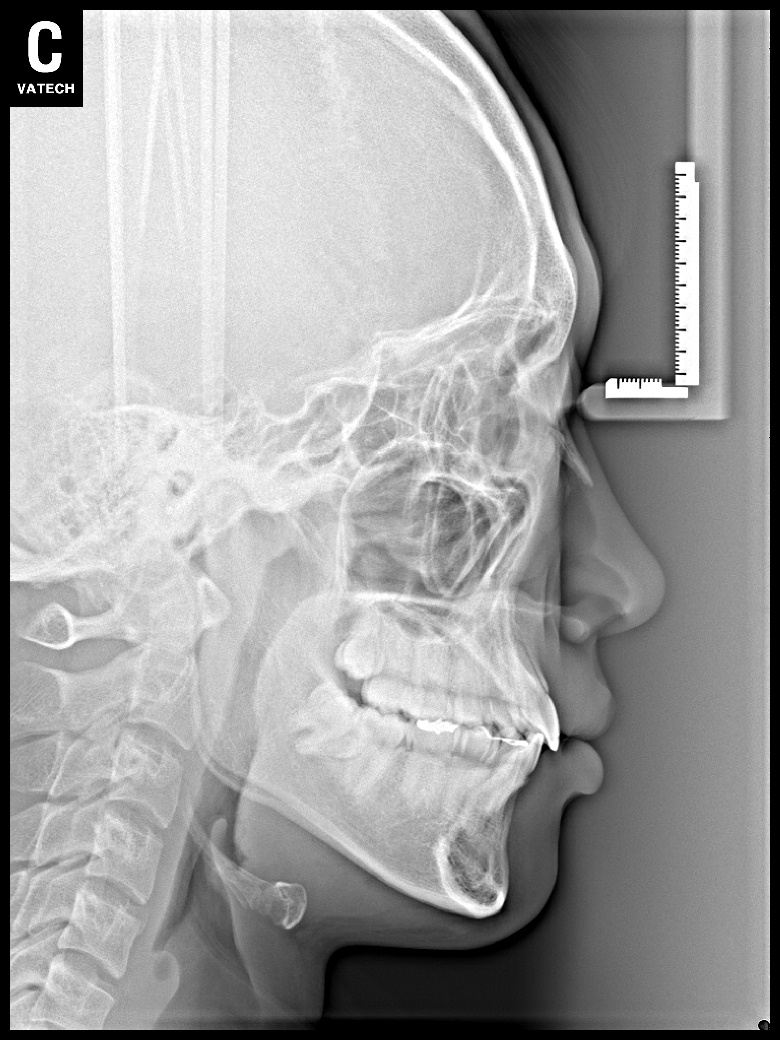

치료 전 사진입니다.